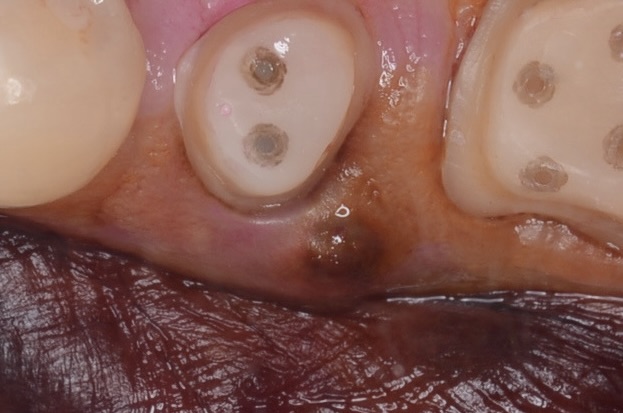

歯茎が腫れる

術後1週間

抜歯即時埋入は、痛みや腫れが少ないです。 -

術後2ヶ月

ジンジバフォーマーを外したところです。綺麗な歯肉ができています。 -